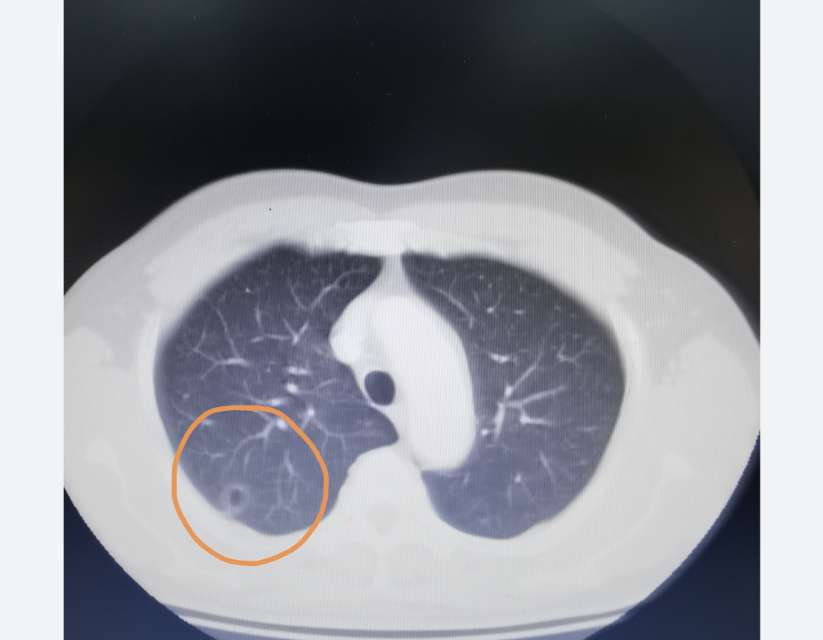

肺ct显示右肺中下叶7mm浅淡结节影,密度不均匀,重建显示为片状病灶